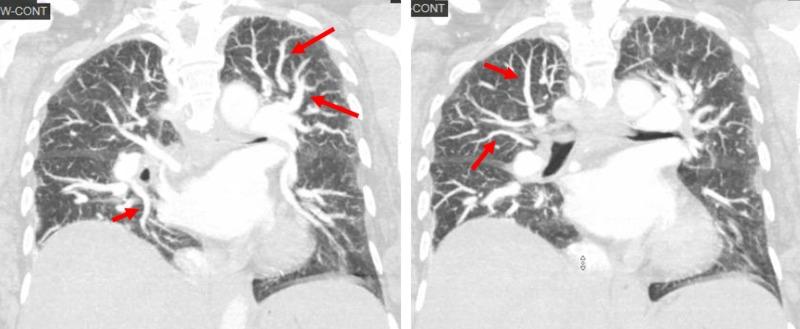

Platypnea-orthodeoxia syndrome (POS) has been defined as shortness of breath and hypoxemia in the upright position that improves with dorsal decubitus. This is a rare disorder caused by right-to-left shunts due to a persistent foramen ovale or pulmonary arteriovenous malformations. Hepatopulmonary syndrome can present with POS in the presence of pulmonary vasodilation and pulmonary arteriovenous communications in patients with liver disease. We report a case where the diagnosis of POS was made incidentally in a patient with cryptogenic liver cirrhosis. After other causes of hypoxemia were excluded, the diagnosis of right-to-left pulmonary shunt was confirmed by late opacification of the left heart chambers seen in a transthoracic echocardiogram. Interestingly, computerized tomography (CT) of the chest with contrast demonstrated a very prominent pulmonary vascular pattern extending to the periphery of the lungs. POS is a rare cause of hypoxemia that requires a high level of suspicion, and exclusion of more common causes of hypoxemia.

平卧呼吸困难-直立性低氧血症综合征(POS)被定义为直立位时出现气短和低氧血症,而在仰卧位时症状改善。这是一种由持续存在的卵圆孔未闭或肺动静脉畸形导致的右向左分流引起的罕见疾病。在患有肝病的患者中,肝肺综合征可在存在肺血管扩张和肺动静脉交通的情况下出现POS。我们报告一例隐源性肝硬化患者偶然诊断为POS的病例。在排除其他低氧血症原因后,经胸超声心动图显示左心腔延迟显影,从而证实了右向左肺分流的诊断。有趣的是,胸部增强计算机断层扫描(CT)显示肺血管纹理非常突出,延伸至肺周边。POS是低氧血症的罕见原因,需要高度怀疑,并排除更常见的低氧血症原因。